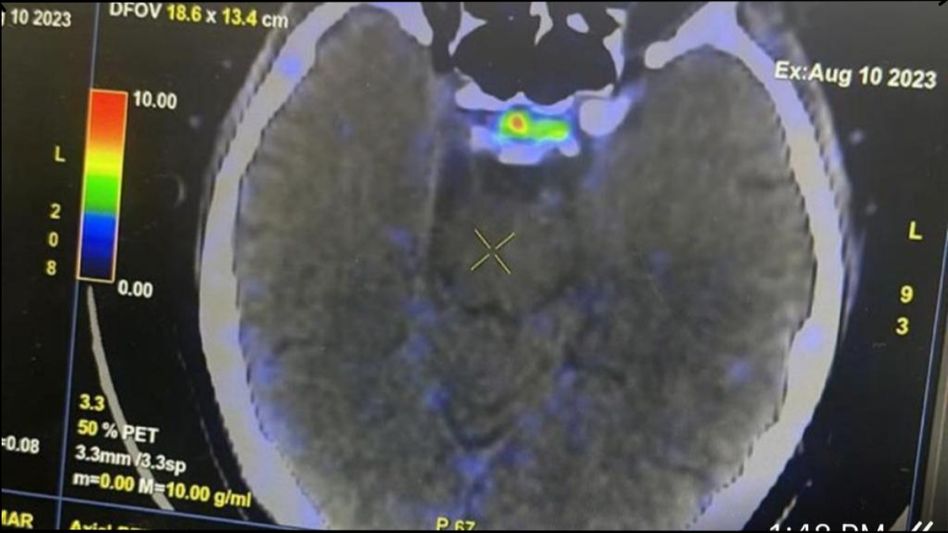

पिट्यूटरी ग्लैंड के अंदर जो सबसे छोटा ट्यूमर होता है पहले उसे एमआरआई और पेट स्कैन के जरिए ढूंढने की कोशिश की जाती थी लेकिन अब इस तकनीक के जरिए बिना चीर फाड़ के बिल्कुल सही जगह पर उसे ढूंढ लिया जाएगा. इस स्कैन और तकनीक की कीमत लगभग 7000 से 9000 रुपये होगी.

पीजीआई की डॉक्टर रमा वालिया और डॉक्टर जया ने इंडिया टुडे को बताया कि ये दवाई इंजेक्शन के जरिए मरीजों के शरीर में दाखिल की जाती है और ये दवा वहीं जाकर अपना असर दिखाती है जहां पर ट्यूमर होता है. क्योंकि ये छोटा ट्यूमर एमआरआई में भी नजर नहीं आता है. शरीर में कई ऐसे ट्यूमर बन जाते हैं जो बहुत छोटे होते हैं और दिखाई नहीं देते, और ये बड़े होकर कैंसर का रूप ले लेते हैं.

ये पता लगाने के लिए कि कुशिंग सिंड्रोम का कारण क्या है और यह कहां से आ रहा है, ट्यूमर का लोकलाइजेशन करना होगा. पिट्यूटरी ग्रंथि में इन छोटे ट्यूमर या कॉर्टिकोट्रोपिनोमा को देखने के लिए हम अक्सर एमआरआई का उपयोग करते हैं लेकिन एमआरआई तस्वीरें हमेशा यह नहीं दिखा सकती हैं कि कुशिंग सिंड्रोम का कारण क्या है या यह कहाँ से आ रहा है. डॉक्टर रमा वालिया ने बताया कि इस दवाई से हमने अब तक 64 मरीजों का इलाज किया है और सभी मरीज बिल्कुल स्वस्थ हैं. उन्होंने कहा कि दुनियाभर से हमें इस दवा के लिए कॉल आते हैं. हमने इस दवा का पेटेंट करवा लिया है.